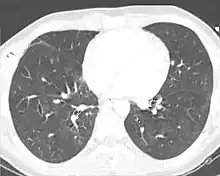

Computed tomography

Computed tomography (CT scanning) is a more sensitive test for pulmonary contusion,[6][33] and it can identify abdominal, chest, or other injuries that accompany the contusion.[38] In one study, chest X-ray detected pulmonary contusions in 16.3% of people with serious blunt trauma, while CT detected them in 31.2% of the same people.[45] Unlike X-ray, CT scanning can detect the contusion almost immediately after the injury.[43] However, in both X-ray and CT a contusion may become more visible over the first 24–48 hours after trauma as bleeding and edema into lung tissues progress.[46] CT scanning also helps determine the size of a contusion, which is useful in determining whether a patient needs mechanical ventilation; a larger volume of contused lung on CT scan is associated with an increased likelihood that ventilation will be needed.[43] CT scans also help differentiate between contusion and pulmonary hematoma, which may be difficult to tell apart otherwise.[47] However, pulmonary contusions that are visible on CT but not chest X-ray are usually not severe enough to affect outcome or treatment.[37]